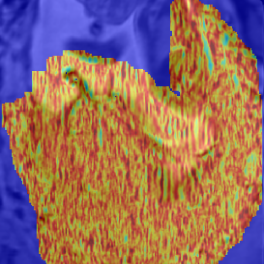

Identification of Rigid Regions and SVR Refinement: The rigidity of regions is measured by keeping track of the probability of each pixel of every . This allows to identify locations best fitting the rigid 2D-3D registration constraints. Integrating and into a 3D volume using the same PSF as for the reconstruction identifies candidate regions, solely containing rigid motion components [26]. This can further be used to initialize the rigid SVR reconstruction or to visualize the data uncertainty during reconstruction.

The evaluation of the reconstruction quality of a whole 3D image into a single-valued metric may not properly reflect the performance differences, as it is based on averaging values of all the pixels of all the input stacks. Furthermore, Tab. I indicates significant differences between variants of PVR but these differences have only minimal qualitative effect on reconstruction accuracy. Therefore, Fig. 12 evaluates the reconstruction quality of PVR additionally using dissimilarity heat maps based on the measured DSSIM (see Sec. IV-A). This approach allows further qualitative evaluation and allows for uncertainty visualization of PVR reconstructions.

PVR surpasses the state-of-the-art SVR method especially for considerable non-rigid deformations. We have evaluated different variants of PVR using fixed-size and multi-size square patches and fixed-size and multi-size superpixels. ANOVA analysis has shown significant differenced between these approaches for different areas of the uterus. However, evaluation of motion compensation methods is difficult especially due to the lack of ground truth in fetal MRI. Mapping the reconstruction quality of a whole 3D volume into a single-valued metric may not properly reflect qualitative differences, as it is based on averaging all measured values of all the input stacks. Therefore, we have performed extensive qualitative analysis and present several examples and evaluation based on structural dissimilarity (DSSIM) heat maps.